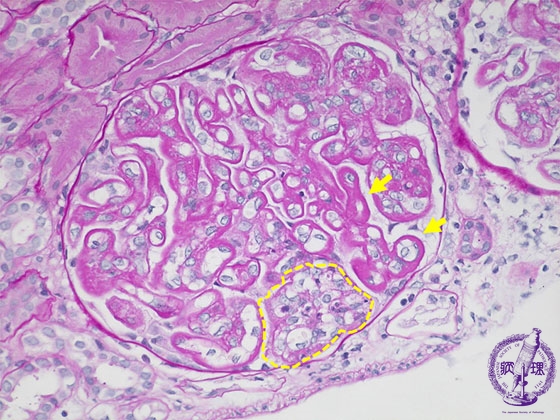

- 12.Kidney and Urinary System

- (6)Lupus Glomerulonephritis

Microscopic findings ( PAS, high power view): The basement membrane is markedly thickened and has a wire-loop appearance (yellow arrows). An endocapillary cellular proliferation containing neutrophil aggregates is focally observed (yellow dotted line).